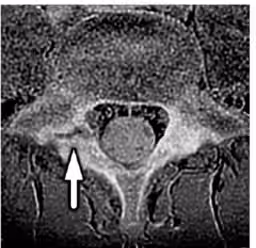

本研究では、12〜14歳の男子サッカー選手107名を対象に、MRIを用いて片側の腰椎分離症の選手19名を抽出し、同条件で年齢・身長・体重を合わせた対照群との比較を行いました。ここで注目されたのは、分離症側の大腰筋が対照群と比較して約12%小さく、また簡便テストで「骨盤が沈む」現象が観察されたことです。

具体的には、3テスラのMRI装置を使用して腰椎の映像を撮影し、体幹筋(大腰筋・多裂筋・脊柱起立筋)の断面積を左右で測定しました。その後、仰向けで片脚を上げるActive Straight Leg Raise(脚上げテスト)と、うつ伏せで脚を上げる股関節伸展テストという2種類の簡便スクリーニングテストを行いました。

その結果、分離症を持つ選手の大腰筋は対照群に比べて小型であることが明らかとなり、さらにASLRテストでは、16名中13名の選手が分離症の兆候を示しました。このことから、片側腰椎分離症の選手は深部筋の左右差や骨盤の安定性が低下している可能性が示されています。